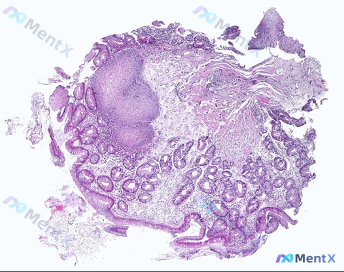

整理了一个临床决策病例,大家来看一看: 55岁男性,因为持续两年的胃灼热就诊,没有胸痛、吞咽困难、体重减轻或者发热,既往没有严重疾病史,日常服用奥美拉唑,生命体征正常,BMI 34kg/㎡,体格检查没有异常,已经完成内镜检查,显示下食管括约肌区域。 现在问题来了:对这个患者来说,管理的下一步最重要的...

来做一道B1型题: 【共用备选答案】 A. Barrett 上皮 B. 胃上皮化生 C. 乳头状瘤 D. 胃黏膜上皮细胞异型增生 E. 黏膜中性粒细胞浸润 【题干】与食管腺癌发病关系密切的病理改变是? 先不忙说解析,第一眼你会选A还是D?或者有人会选B吗?

整理了一个消化科病例,大家先看资料,说下自己的第一判断: 47岁男性,6个月胃灼热、胸痛,疼痛位于胸骨后,一开始只有吃固体食物发作,现在吃液体也痛,抗酸剂已经没法缓解,症状越来越重,这段时间意外体重减轻了2.7kg。 查体全腹检查都正常,实验室检查提示中度贫血,白细胞和血小板都正常。内镜检查看到食管...

整理了一个临床病例,先放资料出来大家一起分析一下: 55岁白人男性,一年多来进食需要将食物切成小块,近期进展到也难以进食汤类液体,近2个月体重减轻4kg,有吸烟史,BMI 26kg/m²,长期用奥美拉唑治反复胃灼热,频繁用布洛芬治背痛。 查体无发热,无咽部炎症、颈部淋巴结肿大,未触及异常甲状腺,已经...

Barrett食管伴肠化生是食管腺癌的明确癌前病变,临床上关于监控和干预的尺度一直有不少模糊的地方:比如低级别异型增生到底是该监测还是直接治疗?T1b期病变能不能只做内镜?哪些操作属于明确的超规范? 我整理了《中国食管癌筛查与早诊早治指南(2022)》等几部权威指南的内容,把从适应症选择到质量控制的...